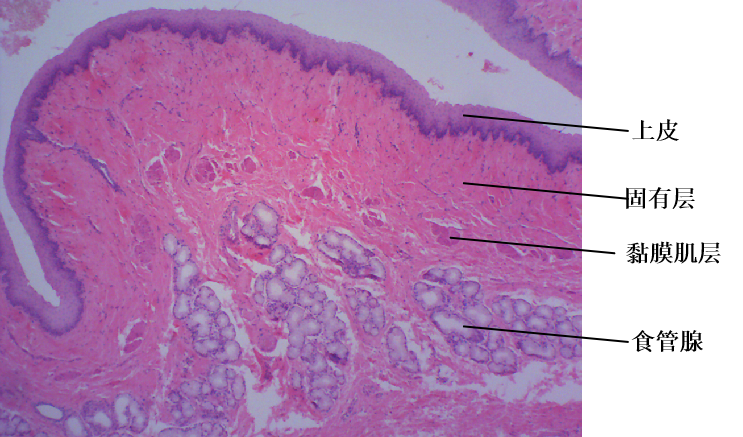

图1. 食管光镜像(HE染色)

食管壁四层结构。黏膜由上皮(复层扁平上皮)、固有层(细密的结缔组织)和黏膜肌层(纵行平滑肌)组成;黏膜下层为结缔组织,可见食管腺;肌层为内环外纵两层;外膜为纤维膜。